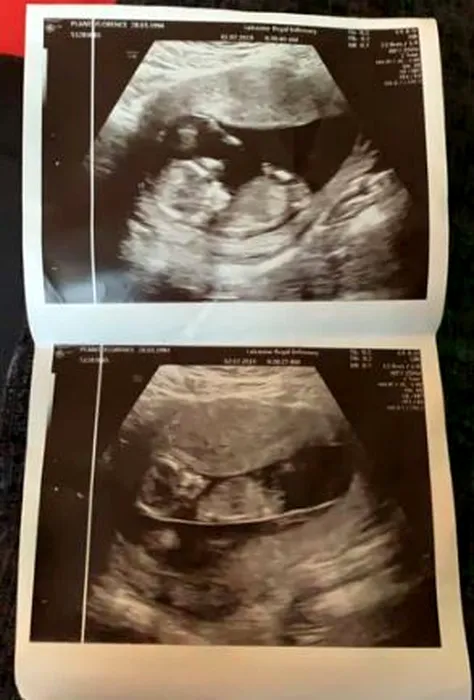

O mamă și-a povestit drama. Și-a purtat bebelușul mort în pântece, pentru ca sora geamănă să supraviețuiască. “O tortură!”